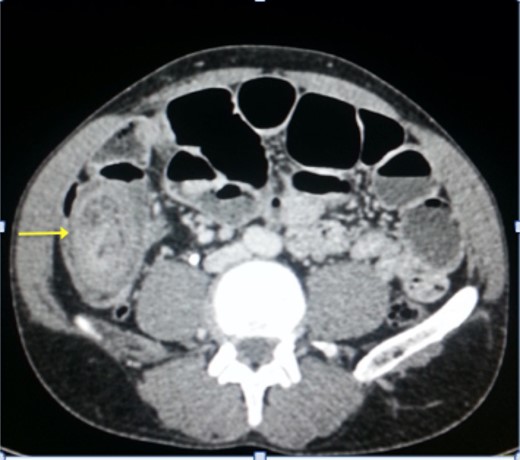

A plain abdominal radiography suggested a bowel obstruction, by showing multiple air-fluid levels. Biological results were the following: hemoglobin: 13,5 g dl−1, hematocrit rate: 42,5%, white blood cell count: 8×103 mm−3, creatinine = 18 mg L−1, serum Na: 139 m Eq L−1, serum K: 3.4 m Eq L−1. The contrast-enhanced CT showed a target mass localized in the right iliac fossa, and was suggestive of ileocecal intussusception without specifying the underlying cause (Fig. 1). While coronal reconstruction showed a « sausage-shaped mass » (Fig. 2). Moreover, there was some lymphadenopathies surrounding the target mass, and a small amount of abdominal effusion.

The classic ‘target mass’ picture on CT scan as found in our case, is pathognomonic of intussusception [6]. It consists in a central dense area and a halo of low attenuation being respectively the intussusceptum and the edematous intussuscepiens [7, 8]. In a sagittal view, we found the classical « sausage sign » in our patient. Moreover, CT scan may identify the underlying cause of the intussusception [1]. The common sites of occurrence of this condition are the junction between the movable segments of the intestine and segments that are relatively fixed as in our case.